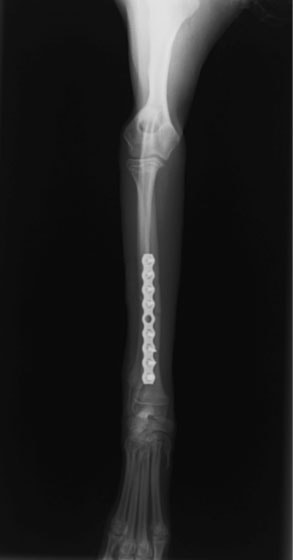

トイプードル 右遠位橈尺骨短斜骨折のALPSによる内固定

Locking Compression Plate

LCPは、スクリュー(ネジ)とプレート(金属の板)をロックする特殊な構造により骨折部位を固定する新しい世代のプレートシステムです。ひとつのホールでロッキングスクリューとスタンダードスクリューの使用を選択できるユニークな構造をしているため、骨折断端間の圧迫を目的とした従来型プレート固定法に加え、高い角度安定性を有するロッキングスクリューを用いた固定法の選択が可能です。従来のプレートシステムでは困難だった部分の骨折や癒合不全の症例に高い治療効果をもたらします。